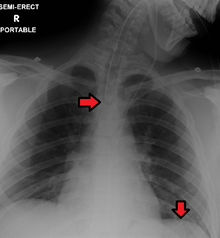

An endotracheal tube and nasogastric tube as seen on CXR. Both in good position.

Great care must be taken to ensure that the tube has not passed through the larynx into the trachea and down into the bronchi. To ensure proper placement it is recommended (though not unequivocally confirmed) that injection of air into the tube be performed,[3] if the air is heard in the stomach with a stethoscope, then the tube is in the correct position. The use of air injected in to the stomach is no longer a satisfactory, safe way of confirming tube position in the UK.[4] There have been instances where this 'confirmation' technique was used and the NGT was in the patients lungs leading to aspiration pneumonia and then death. Another more reliable method is to aspirate some fluid from the tube with a syringe. This fluid is then tested with pH paper (note not litmus paper) to determine the acidity of the fluid. If the pH is 4 or below then the tube is in the correct position. If this is not possible then correct verification of tube position is obtained with an X-ray of the chest/abdomen. This is the most reliable means of ensuring proper placement of an NG tube.[5] The use of a chest x-ray to confirm position is the expected standard in the UK, with Dr/ physician review and confirmation. Future techniques may include measuring the concentration of enzymes such as trypsin, pepsin, and bilirubin to confirm the correct placement of the NG tube. As enzyme testing becomes more practical, allowing measurements to be taken quickly and cheaply at the bedside, this technique may be used in combination with pH testing as an effective, less harmful replacement of X-ray confirmation.[6] If the tube is to remain in place then a tube position check is recommended before each feed and at least once per day.